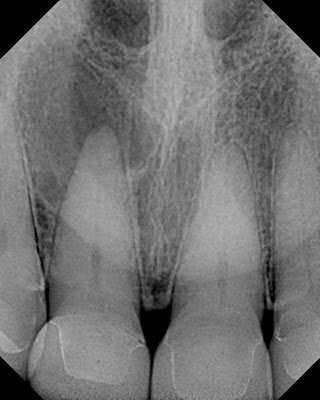

This patient was seen over 3 years ago. Tooth #8 was diagnosed as necrotic w/ acute apical abscess. She had swelling and pain at the time. Antibiotics were prescribed and RCT recommended.

Patient has returned again today with swelling and pain. She reports that she did not have RCT done because the swelling and pain went away. There is no mobility, despite the increased size of the lesion. The RCT has been recommended again. Unfortunately, due to previous experience with root canals, she is convinced that they are less successful than an implant.

Proper understanding of the role of the periodontal ligament with this tooth should help her decide the only acceptable way to treat this tooth is with endodontic treatment.